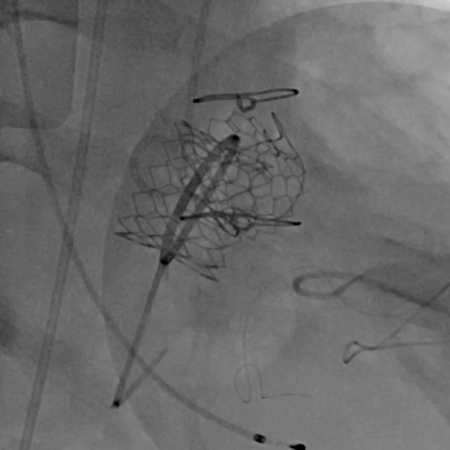

黄焕雷主任带领具有丰富经验的心脏麻醉医师、体外循环师、超声心动图医师、手术室、心外重症监护室、心脏导管室多学科团队,联合心内科专家谢年谨主任,为蔡先生实施小切口下、介入途径的主动脉瓣“瓣中瓣”、二尖瓣“环中瓣”的同期植入手术:黄主任首先在患者左前胸做一小切口,暴露患者的心尖,在跳动的心脏上“绣”上荷包作为介入导管、瓣膜的植入“门户”;随后,黄焕雷主任在超声心动图、放射透视的引导下,将一钢针在患者心尖“扎”入患者心脏内,为之后的瓣膜植入作为引导,具体来说就是将预先选择适合患者大小的生物瓣膜折叠、压缩入细长的输送管道内,好比将瓣膜这一“弹头”安放在输送导管这颗精准制导的“火箭”上,而黄主任的双手则控制这一精准发射和制导,再将瓣膜输送到主动脉合适的位置后释放,新的主动脉瓣便牢固地“卡”在了原有的主动脉瓣架内。经过透视和超声心动图评估,主动脉瓣位置合适,开放、闭合功能良好。随后,黄主任通过这一根钢针和输送导管,利用类似的方式,调整“火箭”的发射轨道,在原有二尖瓣人工瓣环内植入预先选择好大小的二尖瓣生物瓣膜,经过影像学方式评估,新植入的二尖瓣生物瓣工作良好。

球扩释放主动脉瓣瓣中瓣

球扩释放二尖瓣环中瓣